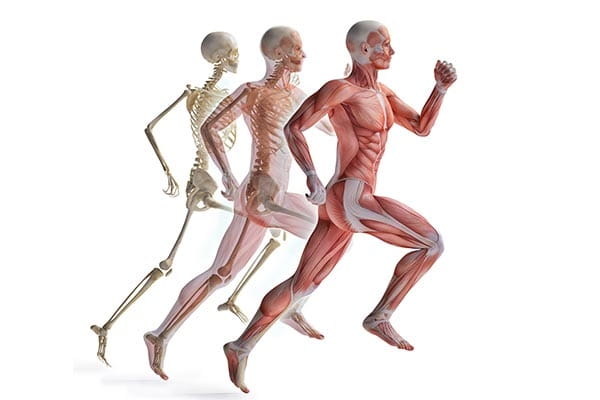

عکس اسکلت بدن انسان با کیفیت. عکس اسکلت عکس اسکلت برای پروفایل عکس اسکلت انسان عکس اسکلت خفن عکس اسکلت بدن انسان با کیفیت عکس اسکلت بدن انسان عکس اسکلت ترسناک عکس اسکلت فانتزی عکس اسکلت فانتزی دخترانه پرچم عکس اسکلت. عکس با کیفیت اسکلت داخلی انسان و درد و گرفتگی در ناحیه استخوان زانو ویژه استفاده در امور تبلیغاتی و تجاری طراحی کاتالوگ بروشور و تراکت با موضوع پزشکی فیزیوتراپی ارتوپد دکتر روماتیسم فیریوتراپ طب فیزیکی. عکس اسکلت بدن انسان زن و مرد آناتومی ساتین 16 سپتامبر 2017. اسکلت داربست بدن است تمام قسمت های بدن روی اسکلت قرارگرفته اند بدن انسان از ۲۰۶ قطعه استخوان تشکیل شده است این استخوان ها طوری با نظم کنار هم قرار گرفته اند که انسان را قادر می سازد حرکات دقیقی داشته باشد.

اسکلت جمجمه و گردن انسان ستون فقرات آناتومی اسکلت جمجمه و گردن انسان ستون فقرات آناتومی تصویر با کیفیت را از لینک زیر می توانید دانلود کنید. ۱ مطلب با کلمه ی کلیدی عکس اسکلت بدن انسان با کیفیت ثبت شده است گالری نسیم جدید ترین و با کیفیت ترین عکس های مناسبتی. عکس با کیفیت آناتومی اسکلت بدن انسان و درد و دیسک در قسمت مهره های ستون فقرات کمر ویژه استفاده در امور تبلیغاتی و تجاری طراحی کاتالوگ بروشور و تراکت با موضوع بیمارستان ها و کلینیک ها و درمانگاه ها و مطب ها پزشکان و.